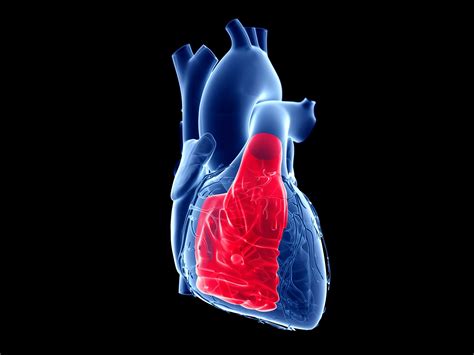

The Right Ventricle Function is a critical, yet often overlooked, component of overall cardiovascular health. While the left ventricle typically receives the most attention for its role in pumping oxygenated blood to the body, the right ventricle serves as the engine for the pulmonary circulation. It is responsible for pumping deoxygenated blood into the lungs, where gas exchange occurs. Understanding how this chamber operates is essential for diagnosing and managing various heart and lung conditions. When the right ventricle is compromised, it can lead to significant systemic issues, making it a focal point in modern cardiology.

The right ventricle (RV) is anatomically distinct from the left ventricle. It is a thin-walled, crescent-shaped chamber that wraps around the left ventricle. Because the pulmonary circulation is a low-pressure system, the right ventricle does not need to generate the same force as the left. However, its complex geometry makes it highly sensitive to changes in pressure and volume.

Proper Right Ventricle Function is paramount for maintaining cardiac output. If the RV fails to pump effectively, blood backs up into the systemic venous circulation, leading to congestion in the liver, gut, and extremities. This condition is clinically recognized as right-sided heart failure.